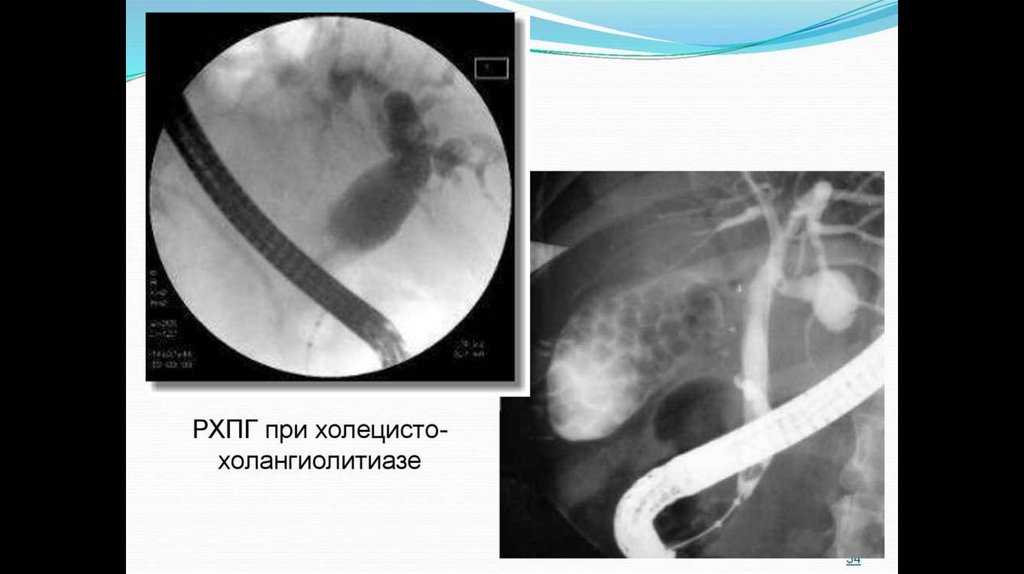

7. РХПГ (эндоскопическая ретроградная холангиопанкреатография)

23. Ретроградная холангиопанкриатография